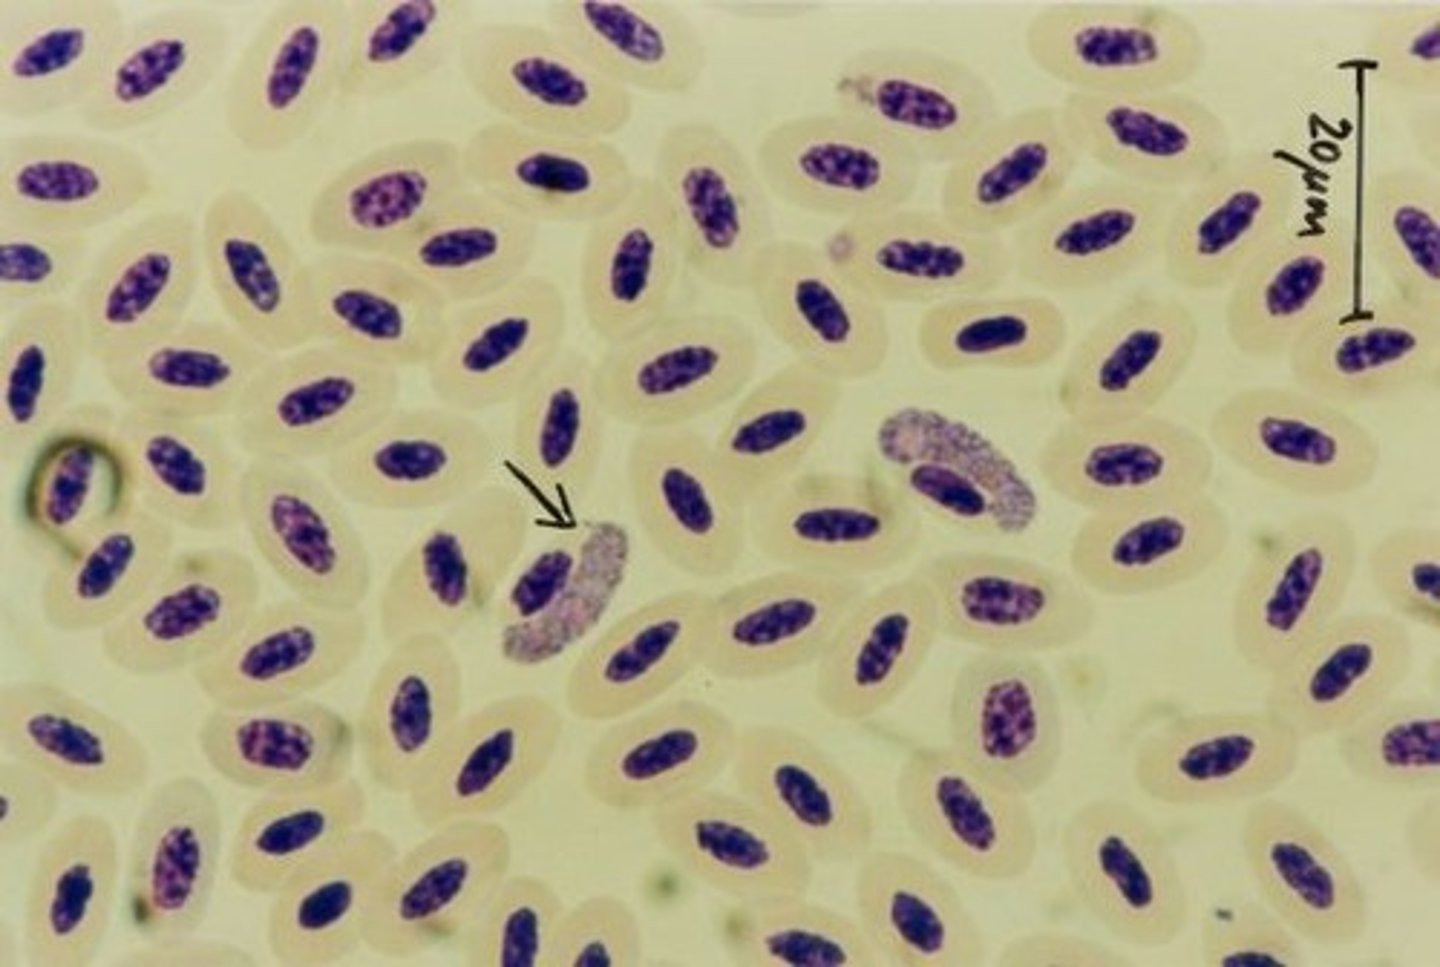

haemorgregarine

exotic hemoparasite

larger than the hosts nucleus

RBC